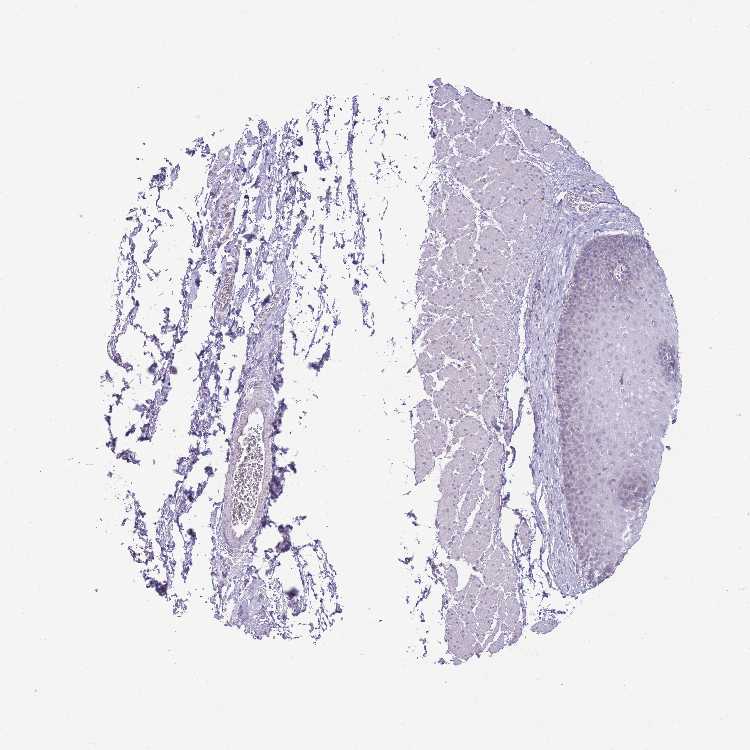

ESOPHAGUS - Antibody stainingi

Antibody staining in the annotated cell types in the current human tissue is reported as not detected, low, medium, or high, based on conventional immunohistochemistry profiling in selected tissues. This score is based on the combination of the staining intensity and fraction of stained cells.

Each image is clickable and will lead to virtual microscopy that enables deeper exploration of all samples and also displays staining intensity scores, fraction scores and subcellular localization as well as patient and tissue information for each sample.

Antibody HPA042632Antibody HPA048484

Squamous epithelial cells MediumNot detected